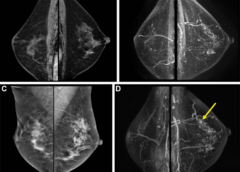

LeggiAssociazione tra BPE e il rischio di un secondo cancro al seno

Le caratteristiche del tessuto mammario evidenti alla risonanza magnetica sono collegate al futuro rischio di secondo cancro al seno nelle donne con una storia personale di cancro al seno, secondo uno studio pubblicato dalla rivista Radiology. Le sopravvissute al cancro al seno con seno…